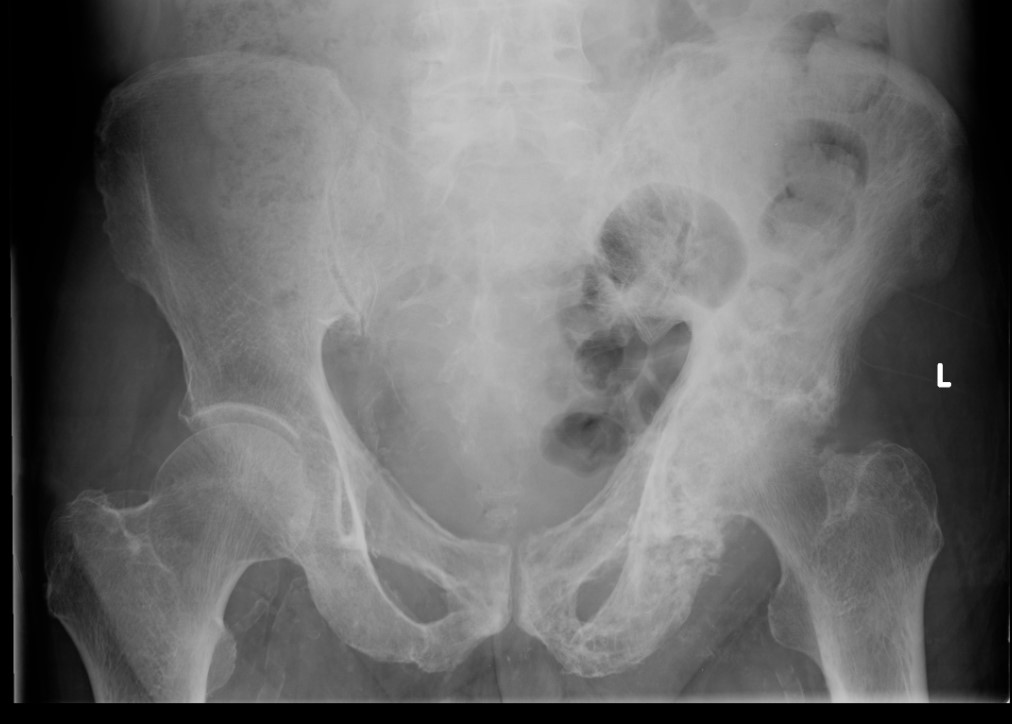

Primary OA: 50%

Secondary OA: 50%

Secondary OA

SUFE Perthes

DDH Protrusio

Trauma

Paget's AVN